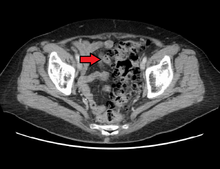

In cases of asymptomatic diverticulosis, the diagnosis is usually made as an incidental finding on other investigations.

- Contrast CT is the investigation of choice in acute episodes of diverticulitis and where complications exist.